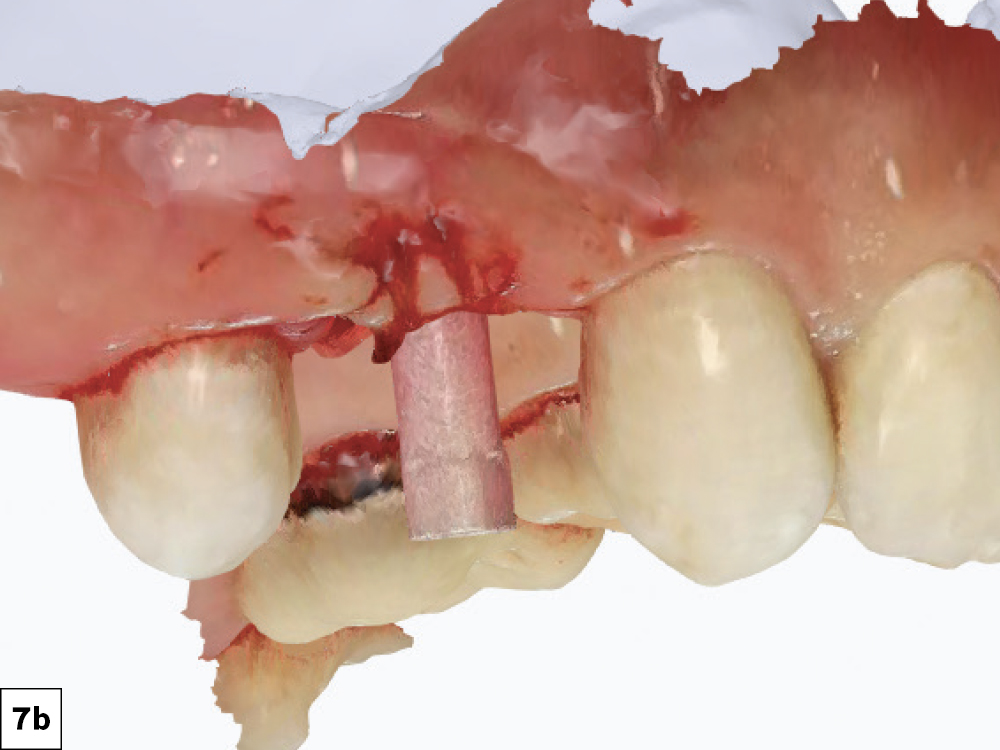

Immediately after placement, scan bodies were threaded in place, and the surgical field was scanned

Figures 7a, 7b: Immediately after placement, scan bodies were threaded in place, and the surgical field was scanned. The scans were imported directly into the fastdesign.io Software and Design Station, the CAD platform that communicates seamlessly with the fastmill.ioIn-Office Mill.